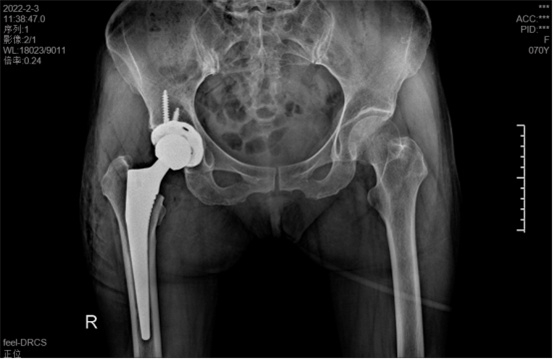

術(shù)中假體植入和術(shù)前規(guī)劃完全一致

術(shù)中,醫(yī)生在患者髂前上棘外側(cè)切開約8cm長的切口,小心翼翼地利用闊筋膜張肌與縫匠肌之間的間隙露出髖關(guān)節(jié)。經(jīng)過一番精細(xì)、高難度的操作,成功植入人工髖關(guān)節(jié)組件,以取代受損的股骨頭和髖臼。由于手術(shù)切口小,肌肉組織未受損,鄭阿姨恢復(fù)很快,術(shù)后第1天就能下床活動(dòng)。